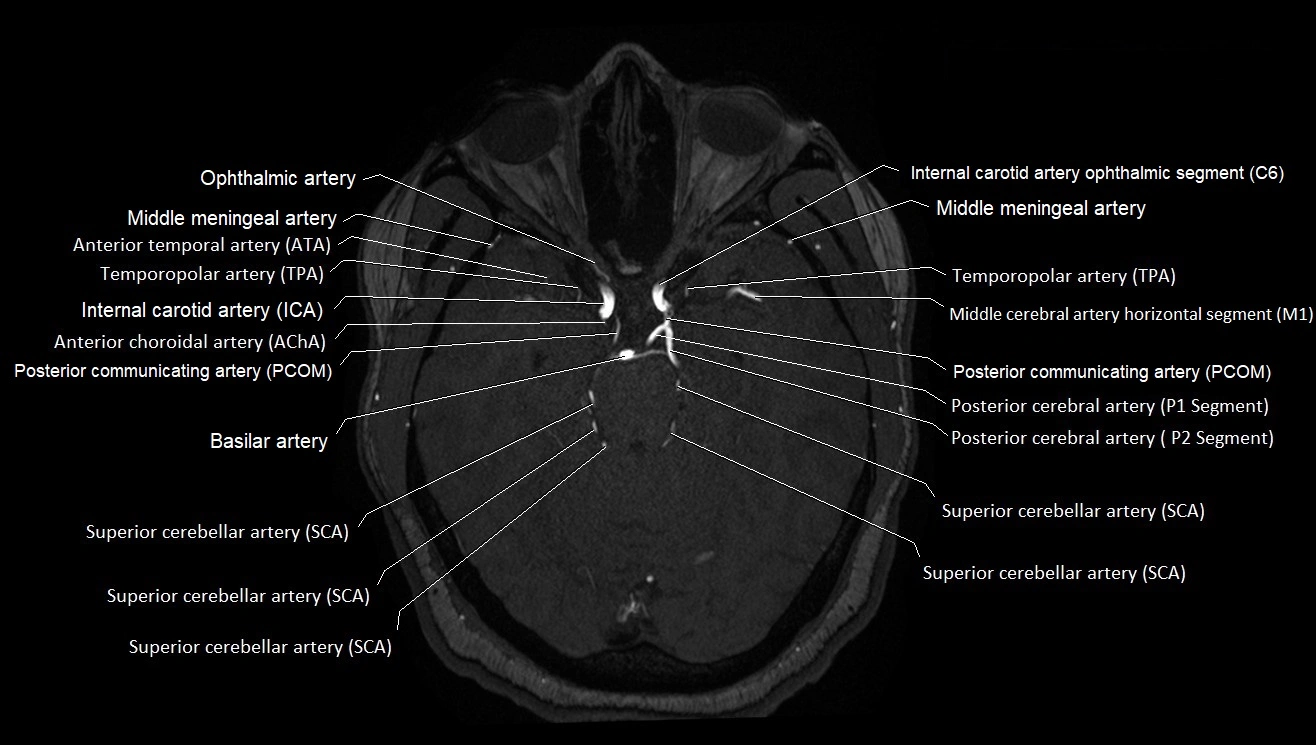

MRI images

image